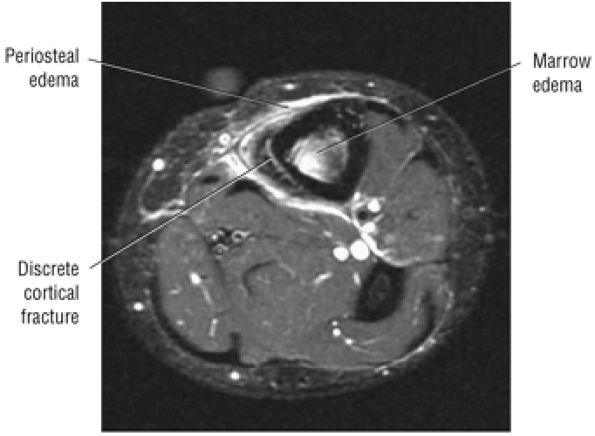

Stage I: Subchondral trabecular compression. Radiograph results are negative, bone scans are posi-tive, and marrow edema is seen on MR imaging (Fig. 5.95).

-